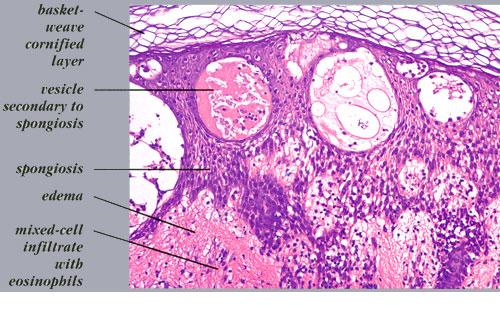

Acute contact dermatitis = التهاب ا لجلدالحاد بالتماس